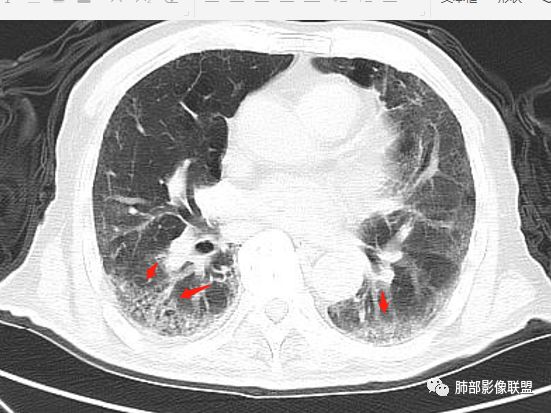

右肺上叶大片实变并散在空洞影,洞壁光滑,张力低,部分实变内可见支气管走形,双下肺散在纤维索条及渗出影,纵隔及肺门淋巴结肿大伴钙化,病史有糖尿病,考虑结核,鉴别:肺克,奴卡,毛霉

老年男性,糖尿病患者,右上肺大片实变,内可见多发虫蚀样空洞,右尖段近胸膜处一空洞内可见一类圆形结节影,支气管扩张,淋巴结肿大,双下肺索条,胸膜增厚。结合糖尿病病史,首选考虑结核干酪性肺炎合并曲霉菌感染,待排肺炎型肺癌

老年男性,糖尿病基础,有咳嗽,喘累症状,病程10天,右上肺大片实变,内虫嗜样,无壁空洞,支气管壁增厚,扩张,淋巴结肿大,胸膜增厚,考虑干酪性肺炎,鉴别粘液腺癌。

老年男性,有糖尿病史,右肺上叶大片实变影,有支气管充气征,支气管走行僵直,有扩张,有多发无壁小空洞和俩个稍大空洞,胸膜稍增厚,双下肺野间质性改变,考虑肺结核,干酪性肺炎可能性大。

老年男性,右肺上叶大片实变,边界局部清楚,局部模糊,其内见支气管充气征及多发大小不等的小泡状及分枝状无壁空洞。双肺下叶磨玻璃样间质性改变。综合考虑右肺上叶结核,干酪性肺炎可能。